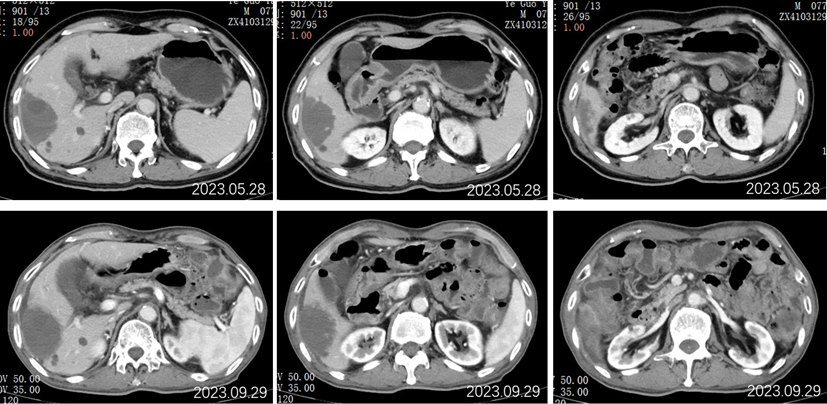

2023.5.28腹部CT增强:肝胆管细胞癌治疗后复查:对比2022-11-25日:1、肝右叶多发占位,较前相仿;2、肝内及双肾多发小囊肿,肝S2小血管瘤,大致相仿;3、慢性胆囊炎改变;胆囊内点状结石未见显示;4、肝内钙化灶;前列腺钙化灶。

2023.09.29腹部增强CT:肝胆管细胞癌治疗后复查:对比2023-05-28日:1、肝右叶多发占位,较前大致相仿;2、肝内及双肾多发小囊肿,肝S2小血管瘤,大致相仿;3、慢性胆囊炎改变;胆囊周围渗出,较前稍增多;4、肝内钙化灶;前列腺钙化灶;新见盆腔少量积液。